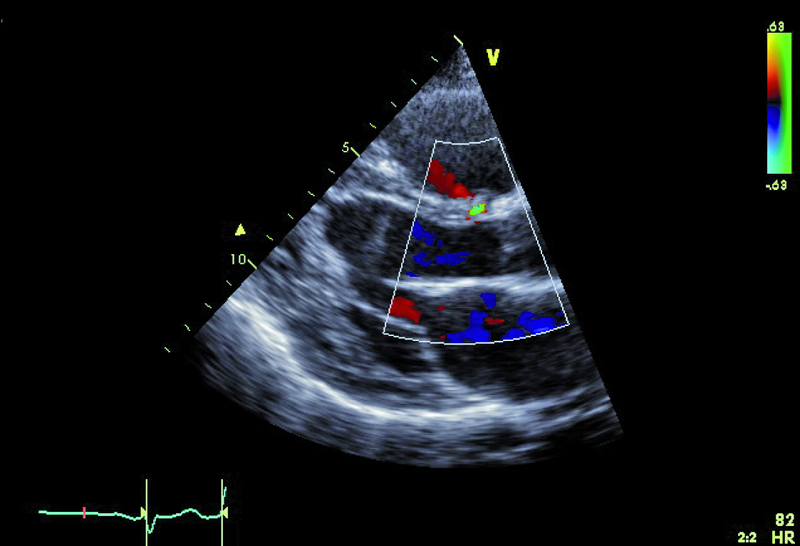

Kobieta, lat 36. Jakie patologie można rozpoznać na zamieszczonych rycinach?

1. Ubytek części błoniastej przegrody międzykomorowej (ryc. 1, 2).

2. Mały przeciek lewo-prawy przez przegrodę międzykomorową (ryc. 1, 2).